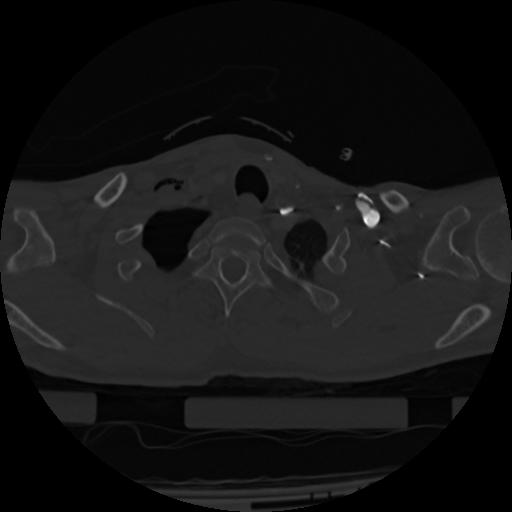

22 ANGIO,CE,Vol,0.5,ANGIO,,